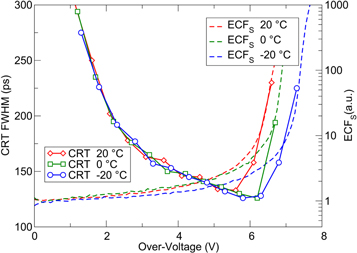

The imaging performance of clinical positron emission tomography (PET) systems has evolved impressively during the last ∼15 years. A main driver of these improvements has been the introduction of time-of-flight (TOF) detectors with high spatial resolution and detection efficiency, initially based on photomultiplier tubes, later silicon photomultipliers. This review aims to offer insight into the challenges encountered, solutions developed, and lessons learned during this period. Detectors based on fast, bright, inorganic scintillators form the scope of this work, as these are used in essentially all clinical TOF-PET systems today. The improvement of the coincidence resolving time (CRT) requires the optimization of the entire detection chain and a sound understanding of the physics involved facilitates this effort greatly. Therefore, the theory of scintillation detector timing is reviewed first. Once the fundamentals have been set forth, the principal detector components are discussed: the scintillator and the photosensor. The parameters that influence the CRT are examined and the history, state-of-the-art, and ongoing developments are reviewed. Finally, the interplay between these components and the optimization of the overall detector design are considered. Based on the knowledge gained to date, it appears feasible to improve the CRT from the values of 200–400 ps achieved by current state-of-the-art TOF-PET systems to about 100 ps or less, even though this may require the implementation of advanced methods such as time resolution recovery. At the same time, it appears unlikely that a system-level CRT in the order of ∼10 ps can be reached with conventional scintillation detectors. Such a CRT could eliminate the need for conventional tomographic image reconstruction and a search for new approaches to timestamp annihilation photons with ultra-high precision is therefore warranted. While the focus of this review is on timing performance, it attempts to approach the topic from a clinically driven perspective, i.e. bearing in mind that the ultimate goal is to optimize the value of PET in research and (personalized) medicine.

where c is the speed of light in vacuum and  the coincidence resolving time (CRT). The CRT characterizes the capability of a pair of detectors to resolve the difference in the times of interaction of two gamma quanta detected in coincidence. It is commonly quantified as the full-width-at-half-maximum (FWHM) of the spectrum of time differences measured for a large number of coincidences. Currently available TOF-PET scanners have coincidence resolving times of several hundred ps FWHM (averaged over the entire system). This is still insufficient to assign the annihilation event directly to a single image voxel. Nevertheless, the available TOF information can be used to limit the number of voxels to which activity is attributed during image reconstruction. This improves the quality of the resulting image in various ways, as discussed further in the following.

the coincidence resolving time (CRT). The CRT characterizes the capability of a pair of detectors to resolve the difference in the times of interaction of two gamma quanta detected in coincidence. It is commonly quantified as the full-width-at-half-maximum (FWHM) of the spectrum of time differences measured for a large number of coincidences. Currently available TOF-PET scanners have coincidence resolving times of several hundred ps FWHM (averaged over the entire system). This is still insufficient to assign the annihilation event directly to a single image voxel. Nevertheless, the available TOF information can be used to limit the number of voxels to which activity is attributed during image reconstruction. This improves the quality of the resulting image in various ways, as discussed further in the following.

A general framework for describing the factors that affect the time resolution of scintillation detectors was introduced at the beginning of this chapter. Figure 3 provides a schematic overview of the pertinent processes and the functions and parameters used to describe them. These can be classified according to whether they relate to the emission, transfer, or detection of scintillation photons. The stochastic nature of these processes warrant Monte Carlo modeling (section 2.1), even though it may take considerable effort to obtain all required input parameters with sufficient accuracy. Several authors have proposed analytical models of scintillation detector time resolution, which vary in the level of detail in which the three categories of processes are described (section 2.2). In section 2.3, it was argued that photon-counting statistics form the dominant contribution to the CRT of state-of-the-art TOF-PET detectors based on bright scintillators and photosensors with high internal gain. As a consequence, the CRLB on the time resolution provides a useful measure of the achievable time resolution. The CRLB can be used, for example, to better understand fundamental limitations, to benchmark detector performance, and to make rational design choices in the development of detectors, detector components, and timing algorithms.

A number of general conclusions can be drawn from the currently available theory. It is emphasized that these apply to detectors based on fast and bright scintillators (some observations relevant to other cases are discussed in section 5.5). The CRT is proportional to  in this case. This, in turn, implies that

in this case. This, in turn, implies that

and

and  all are equally important for optimum time resolution. Furthermore, if

all are equally important for optimum time resolution. Furthermore, if  is much larger than each of the scintillator rise time, the OTTS, and the SPTR, as is commonly the case, the CRT is also proportional to

is much larger than each of the scintillator rise time, the OTTS, and the SPTR, as is commonly the case, the CRT is also proportional to  In first order approximation,

In first order approximation,  therefore is a useful FOM for optimizing the intrinsic properties of a TOF-PET scintillator. The scintillator rise time only becomes important if it is larger than both the OTTS and the SPTR, in which case the CRT also becomes proportional to

therefore is a useful FOM for optimizing the intrinsic properties of a TOF-PET scintillator. The scintillator rise time only becomes important if it is larger than both the OTTS and the SPTR, in which case the CRT also becomes proportional to